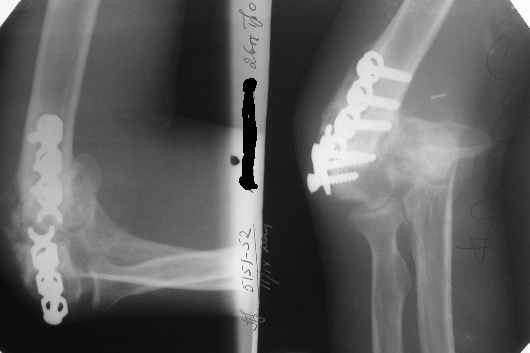

The recent x rays show established Non union with poor quality bone in the distal fragement. The joint is also appearing degenerate. In view of the multiple failed reconstructive surgeries, an Elbow replacement would seem reasonable.

However it would have to be a fully constrained one as there would be missing bone stock.